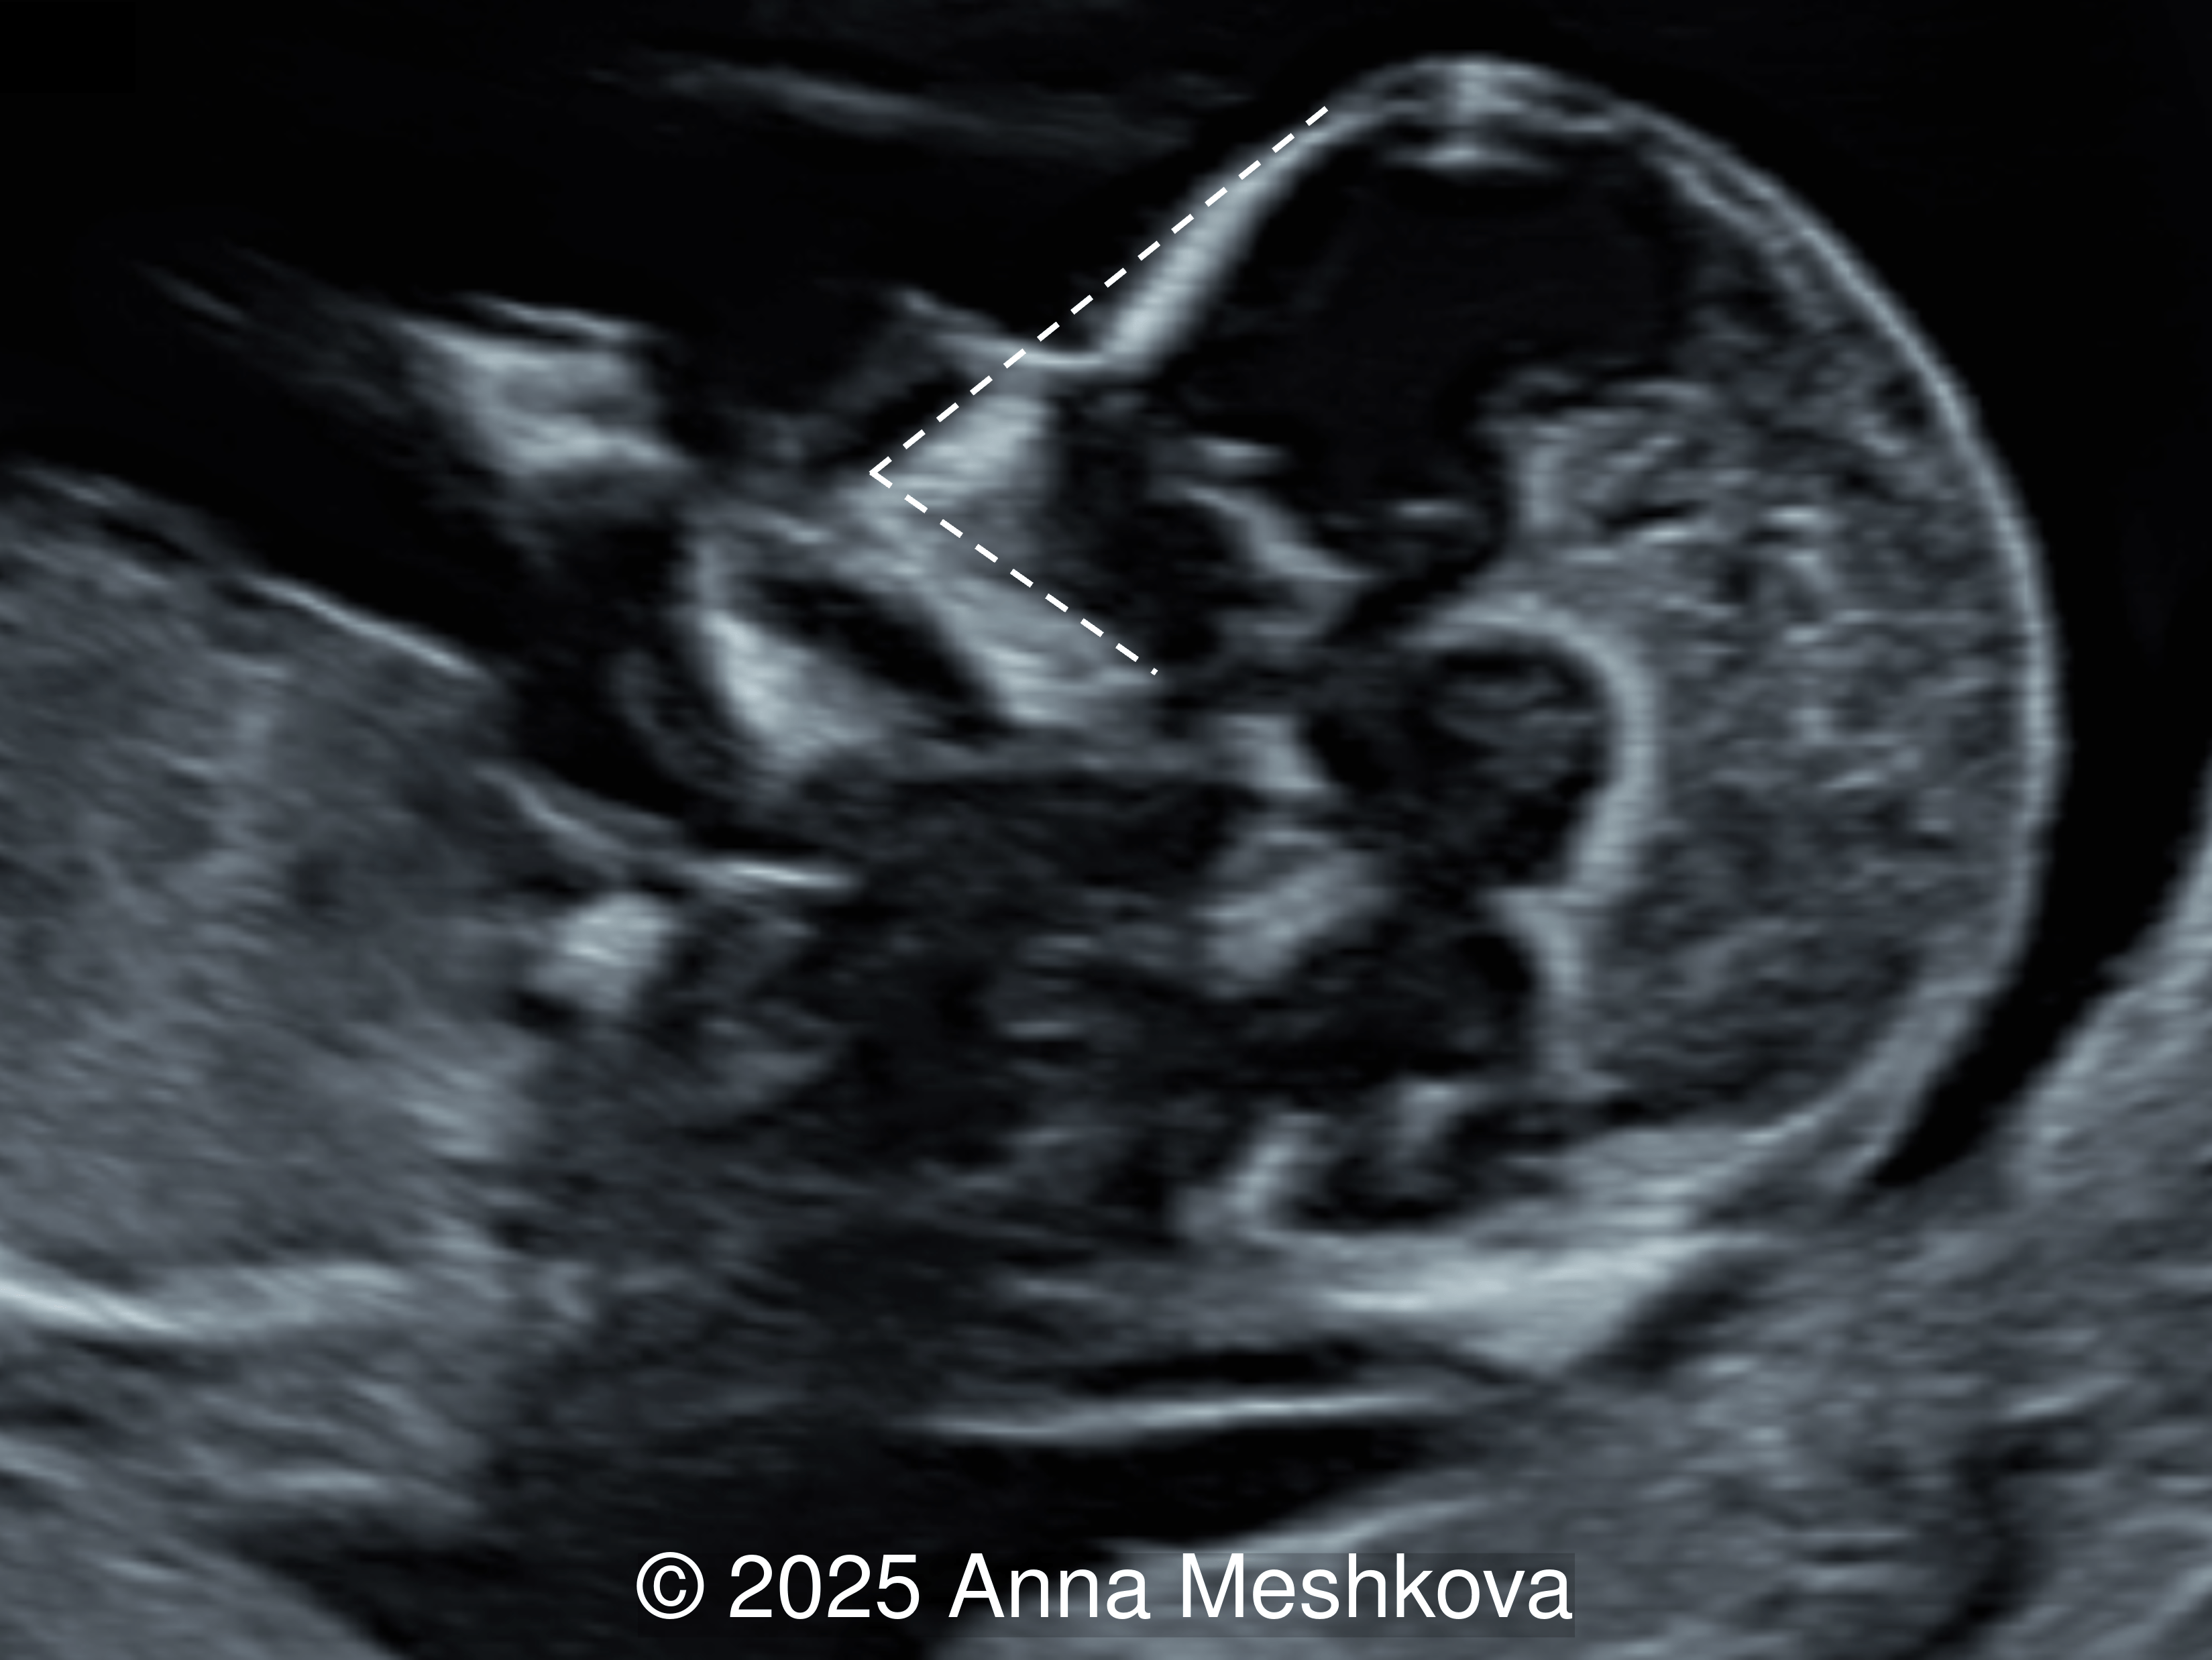

• Image 3, Video 1: Mid-sagittal image demonstrating the mid brain and brain stem displaced posteriorly, known as the "crash" sign. Intracranial translucency is difficult to visualize.